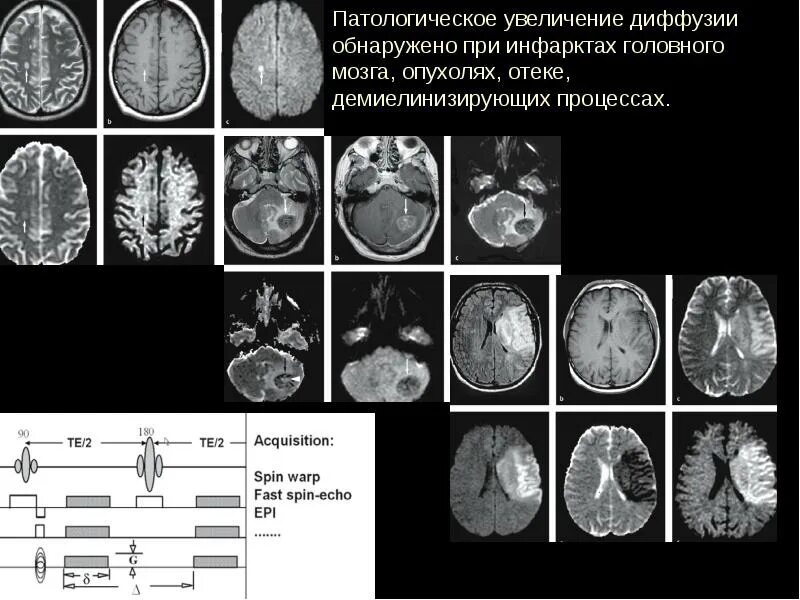

Мрт диффузия всего тела